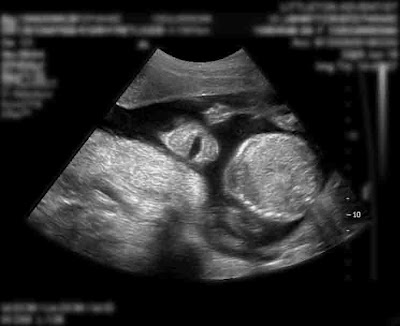

Oh yeah – and my oldest brother and his wife are having a baby! Here is a photo of him smiling!!!! How AMAZING is that? Even tiny babies are having fun!